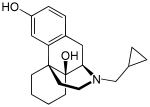

Others

- 1-Nitroaknadinine * 14-episinomenine

- 6-Keto Nalbuphine

- Nalbuphine

Structures

| Other Morphinans | ||||

6-Keto Nalbuphine 6-Keto Nalbuphine |

Nalbuphine Nalbuphine |